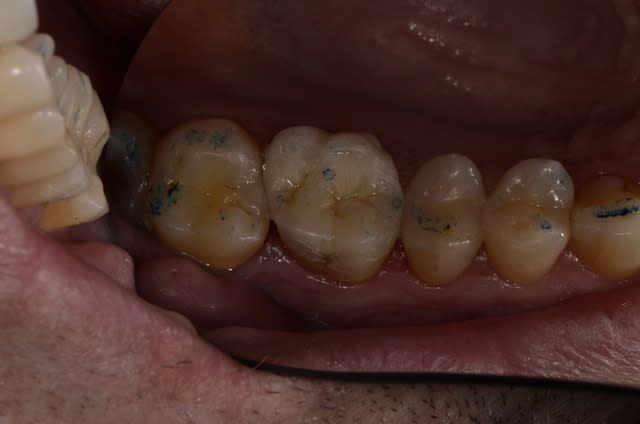

Je me permets de vous balancer un petit cas clinique à discuter au sujet d'un ONLAY sur 46, chez une patiente de 55 ans.

Dent 46 vivante, qui présentait un amalgame occlus-mésio-dital vieux de 15 ans, et une fracture (classique) de tout le pan lingual m'a poussé à restaurer cette dent.

Importante perte de substance.

J'ai décidé de conserver la dent vivante (une erreur de jeunesse ?! j'suis jeune diplômé..) : préparation sous anesthésie, mise en place un fond de cavité CVI (Fuji IX), avant de réaliser une empreinte pour ONLAY COMPOSITE.

Puis, au RDV suivant, onlay collé au DEXTACEM (colle auto-adhésive).

Quel est votre point de vue :

* sur l'indication de l'inlay au vu de l'état résiduel de la dent ?

* sur ce matériau de collage (vu qq CD utilisant ce matériau pour le collage) ?